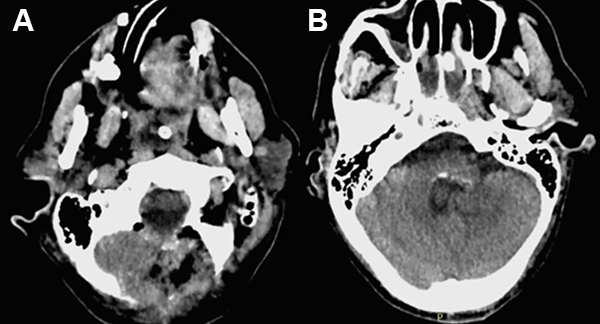

Paciente masculino de 71 años de edad, tabaquista de larga data. Consulta por inestabilidad en la marcha y cefalea holocraneana intermitente. Al examen se muestra vigil, desorientado, con alteración de la memoria a corto plazo, marcha magnética e incontinencia urinaria. Se realiza TC contrastada y posterior RM de cerebro con gadolinio objetivándose lesión espacio ocupante hipo-isointensa de 10 cc. aprox. ocupando el 4to ventrículo, con realce intenso a la administración de contraste y ventriculomegalia asociada (índice de Evans de 0,43) con edema transependimario (figs. 1 y 2).

Figura 1: TC axial con contraste evidenciando lesión hiperdensa con captación intensa y heterogénea.

Las características tomográficas son bien definidas; aparece como una masa lobulada, hiperdensa en relación al parénquima adyacente y realce homogéneo e intenso a la administración de contraste. En RM se muestran isointensos en T1 e iso-hipointensos en T2, con marcado realce a la administración de gadolinio. Puede poseer áreas de baja intensidad de señal que se corresponden a calcificaciones. Los signos angiográficos pueden incluir la presencia de múltiples arterias espiraladas como si se tratara de un meningioma; con realce en fase arterial temprana y persistencia en fase venosa, desplazamiento de vasos como la vena cerebral interna evidenciando dilatación ventricular.8